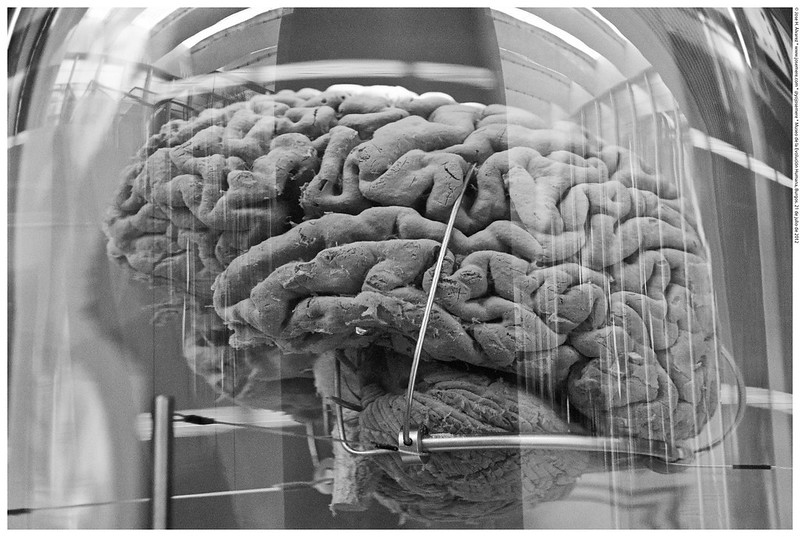

Aunque el canibalismo cesó poco después, aún hubo casos de kuru entre los Fore durante años, ya que la enfermedad tenía un periodo de incubación muy largo, ¡incluso de medio siglo! Y si hablo de periodo de incubación estoy dando a entender que la enfermedad es, en efecto, infecciosa. Gajdusek quiso probarlo y para ello se llevó tejido cerebral infectado a su laboratorio y lo inyectó en chimpancés.

Los pobres monetes desarrollaron kuru validando la hipótesis del investigador, lo que le valió el Premio Nobel en Medicina en 1976. Pero, ¿qué causaba el kuru? ¿Una bacteria? ¿Un hongo? ¿Un virus,quizá? Nada de eso. El investigador Stanley Prusiner descubrió que el agente que originaba la patología era algo totalmente desconocido, casi extraterrestre: se trataba de una proteína que tenía la capacidad de infectar transmitiendo su plegamiento erróneo a otras proteínas cerebrales, causando neurodegeneración. Estas proteínas o priones son responsables de la enfermedad de las vacas locas, la enfermedad de Creutzfeldt-Jakob (su variante humana) o el insomnio fatal, una enfermedad muy rara y mortal inusualmente prevalente en Álava.